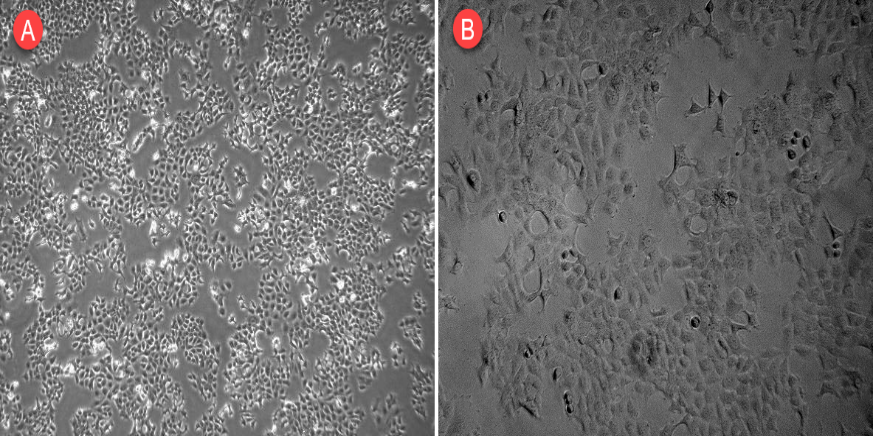

MCF-7, a human breast cancer cell line was cultured in DMEM supplemented with 10% FBS (foetal bovine serum) and 1% penicillin/streptomycin at 37 °C in a humidified atmosphere with 5% CO2. The cells were trypsinized, resuspended in complete media (DMEM with FBS and antibiotics), and counted at 80% confluence to determine cell density. A phase-contrast microscope (Olympus CKX41) was used to evaluate the overall appearance of the cells. Microphotographs were obtained with objectives 4 and 10, respectively [20].

Fig. 9: Exhibits the morphological properties of MCF-7 cells, with the magnification of the A and B images being ×4 and ×10, respectively